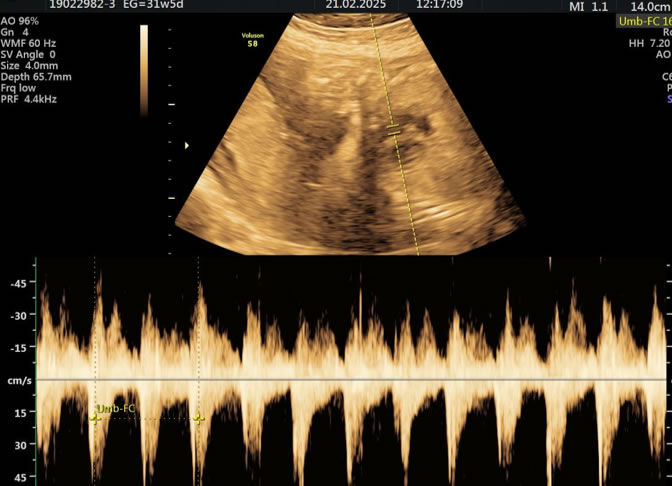

Es una técnica especializada de ultrasonido que utiliza el efecto Doppler para evaluar el flujo sanguíneo en el sistema circulatorio del feto y la madre durante el embarazo.

Se usa principalmente para evaluar el flujo sanguíneo en la placenta, el cordón umbilical y los vasos sanguíneos de la madre y el feto. Esto proporciona información valiosa sobre la salud del embarazo y la circulación fetal.

• Eco Doppler III Trimestre